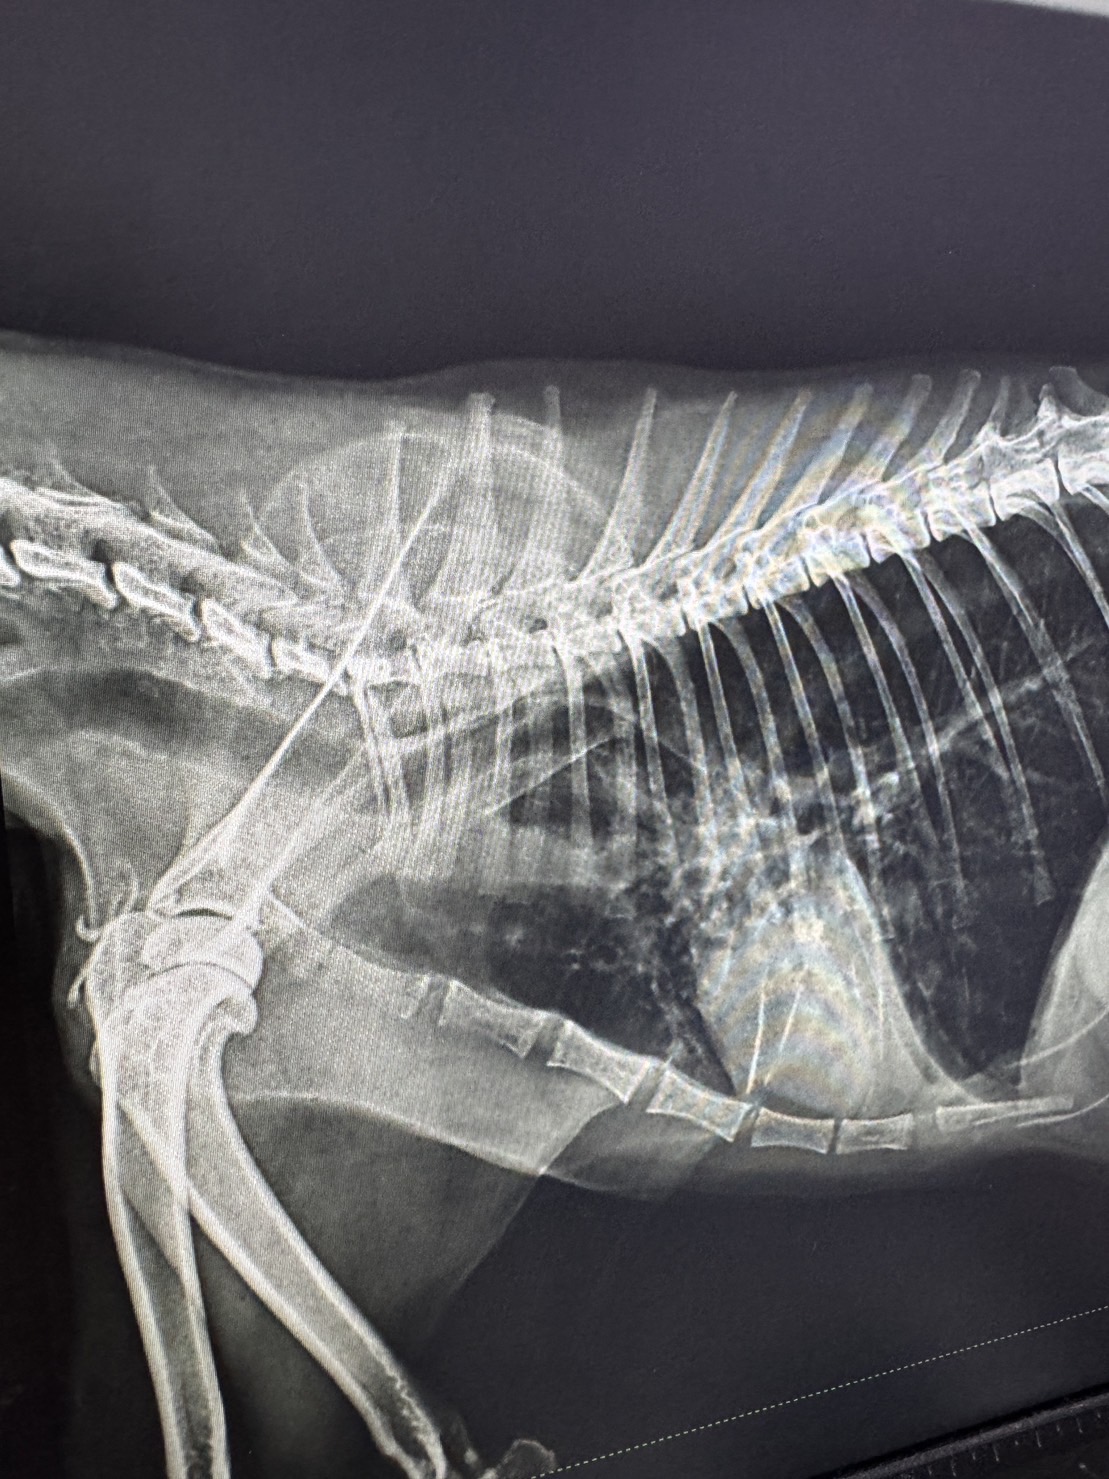

上個月的超強寒流來襲深虎突然呼吸聲很急促,夥伴們觀察跟討論後決定要帶深虎回台北到我們熟悉的獸醫院

醫生檢查後發現肺部有發炎的狀況,無法排除是天氣造成的肺部感染還是腫瘤,因此深虎目前先住在醫院接受更完善的治療跟照護!